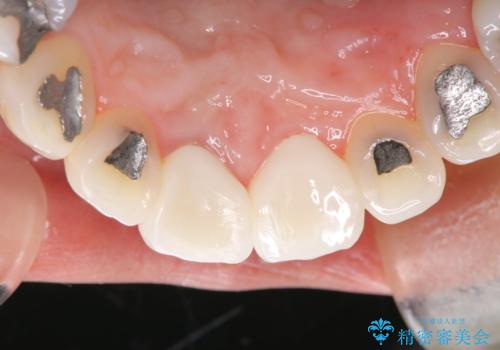

破折した器具を除去したのち、根管治療、ファイバーコア築造、セラミッククラウンの製作を行いました。

歯の根に器具が残っている事にビックリされていました。

セラミックは、2本行う事でより自然な仕上がりとなり、患者様もご満足していただけました。